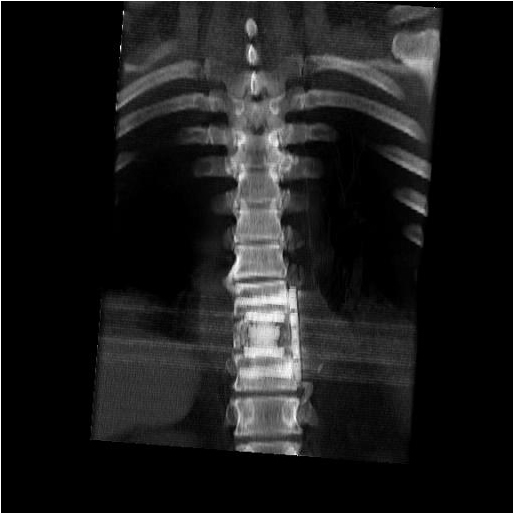

After completion of the spinal procedure, reorientation of the thoracic surgeon by the spinal surgeon is performed, including visualization of the implanted hardware and an explanation of the procedure that was performed (Figures 9a-c). Hemostasis is secured, the chest irrigated, and the posterior mediastinum is inspected for lymph leak (the presence of a CSF leak must be ruled out by the spine surgeon prior to this point in the operation). The diaphragm, if mobilized, is reattached to the fascia of the posterior chest wall with interrupted horizontal 0 prolene sutures or is anchored around the rib. A 28 Fr chest tube is placed in the posterior mediastinum and the chest is closed in a standard fashion. Postoperative spine imaging is necessary to demonstrate adequate position of the hardware and correction of the vertebral defect (Figures 10a-e, Video).

| Figure 10a-e: CT of spine after fixation | Figure 10b | Figure 10c |

| Figure 10d | Figure 10e |